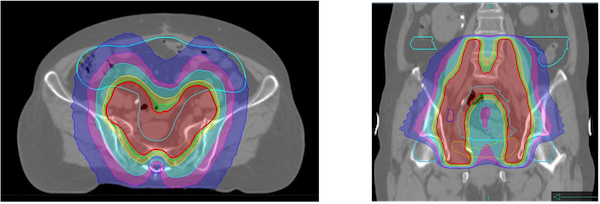

腸管への被ばく線量を低く抑えた治療が行えます。